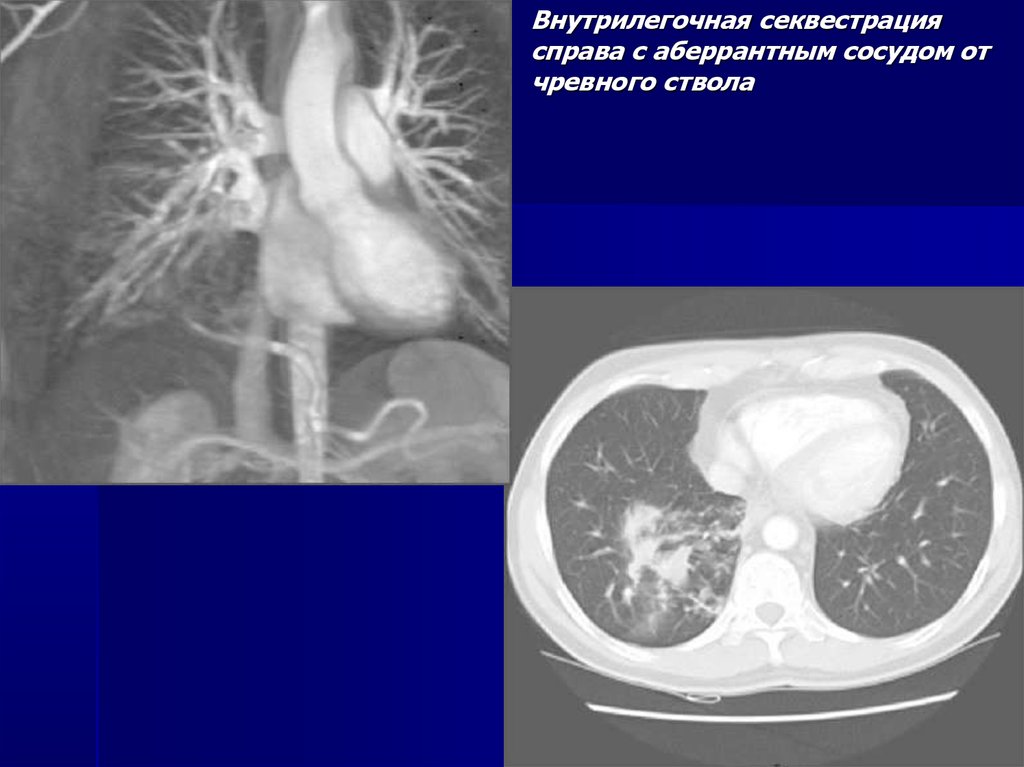

Внутрилегочная секвестрация

справа с аберрантным сосудом от

чревного ствола